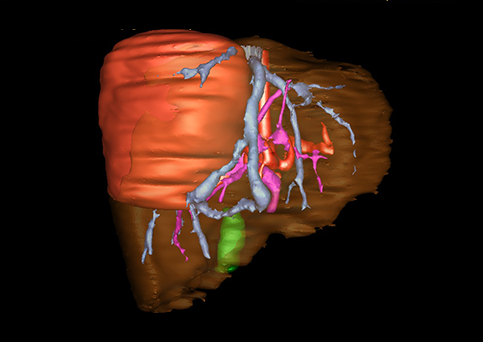

近年来由于数字医学的发展,基于可视化三维重建技术的计算机辅助手术系统极大推进了小儿肝脏肿瘤的精准手术的进步。可以立体透视肝脏解剖、精确掌握肝段的边界、精确测算肝段乃至任意血管所支配的功能体积、准确定位病灶及其与邻近血管的解剖关系,最终对不同手术方案进行比较、筛选和优化。因此,计算机辅助手术规划系统是实现精准肝切除的有力辅助工具,是未来数字外科、精准外科等21世纪外科新理念的重要技术支撑。

计算机辅助手术规划系统具有良好的操作可行性、计算准确性和三维显示效果,可半透明、交互式显示真实的肝内立体解剖关系和空间管道变异,准确计算肝内管道的直径、走行角度,两点间的垂直距离,和任意血管的支配或引流范围等传统二维影像无法获取的信息,有助于实施个体化手术,提高了手术的确定性、预见性和可控性。计算机辅助手术规划系统可直观显示预留肝脏的结构和功能,并可通过虚拟切割功能辅助术者对手术方案进行蹄选和优化,系统评估手术风险和制定对策,改变了部分二维规划的术式和切除范围,使部分二维规划认为不能切除的患者成功手术,提高了手术的根治性、安全性和病变的可切除性,更加符合精准肝脏外科的术前规划要求。详见第11章。

随着计算机技术及影像检查技术的不断发展,以精确的术前影像学和功能评估、精细的手术操作为核心的精准肝切除技术日益受到重视。基于数字医学的计算机辅助手术技术(computer-assisted surgery,CAS)则是实现肝脏精准手术操作的基础。计算机辅助手术系统(CAS)可将术前二维(two dimensional,2D)的CT/MRI影像数据进行三维(three dimensional,3D)重建,建立个体化的肝脏三维解剖模型,清晰显示肝脏内脉管系统的走行及解剖关系,还原病灶与其周围脉管结构的立体解剖构象,准确地对病变进行定位、定性和评估,制定合理、定量的手术方案,实施个体化的肝脏血管取舍分配方案及实施精准肝脏手术。一般认为CAS包括:创建虚拟的患者的图像;患者图像的分析与深度处理;诊断、手术前规划、手术步骤的模拟;术中实时导航。应用本技术后,由于可以更清晰地看出肿瘤的界限,特别是根据肝血管的显影,判断出肿瘤与门静脉及肝静脉的关系以在手术前较准确地估计出手术成功切除的可行性。以往部分根据普通强化CT判断无法手术的病例而被评估为可以成功切除并手术成功。

图23:肝中叶肿瘤二维CT图像